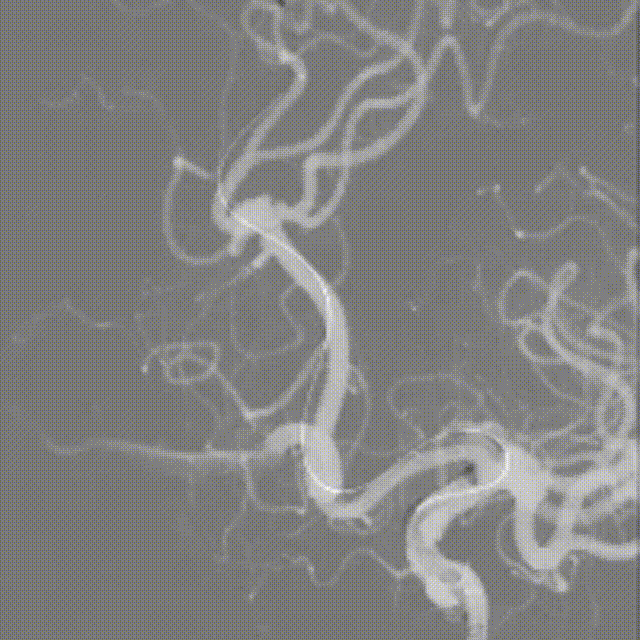

支架全段打开。

支架全段打开造影。

术后造影。

术后正侧位造影。

强易达(Choydar)血流导向密网支架材质是镍钛合金,输送易到位;头端导丝、50%释放点、100%释放点清晰,便于观察支架位置。

50%Mark点可帮助分析后半段打开后的尾端位置,近端血管较粗考虑支架短缩,也可调整支架的50%Mark点置于偏近端一些。

支架由2对4根铂钨合金显影丝以对向排列的方式,混合编入支架主体,呈3D立体显影效果,便于观察支架贴壁情况。